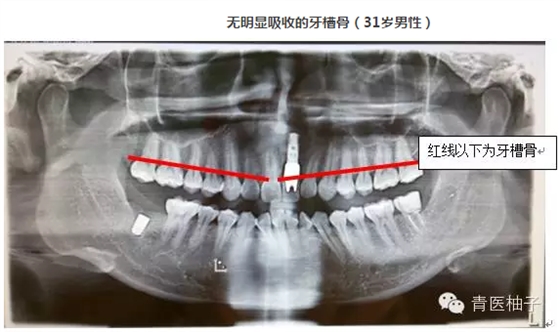

牙周病是指發(fā)生在牙支持組織(牙周組織)的疾病,包括僅累及牙齦組織的牙齦病和波及深層牙周組織(牙周膜、牙槽骨、牙骨質(zhì))的牙周炎兩大類。牙周疾病是常見的口腔疾病,是引起成年人牙齒喪失的主要原因之一,也是危害人類牙齒和全身健康的主要口腔疾病。